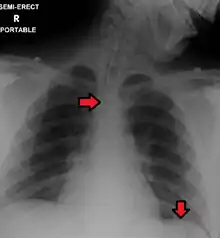

Confirming placement

It is necessary to confirm placement of the endotracheal tube to ensure that the tube is properly positioned within the trachea and has not accidentally passed into the esophagus instead. Additionally, it is important to confirm that the endotracheal tube was not placed too deep in the trachea where is may only be ventilating one of the lungs due to it being positioned within a mainstem bronchi (frequently the right mainstem bronchi due to a more obtuse angle than the left). The gold standard for confirming successful placement of an endotracheal tube is direct visualization of the tube passing through the vocal cords and positive end-tidal carbon dioxide on capnography. Secondary methods of confirmation include oxygen saturation, chest x-ray, ultrasound, condensation in the endotracheal tube, equal chest rise, breath sounds heard on both sides of the chest (often with the assistance of a large tidal volume breath), and an absence of breath sounds over the epigastrium. No single method of confirming placement is 100% reliable so multiple methods of confirmation should be utilized.[6][13][14]